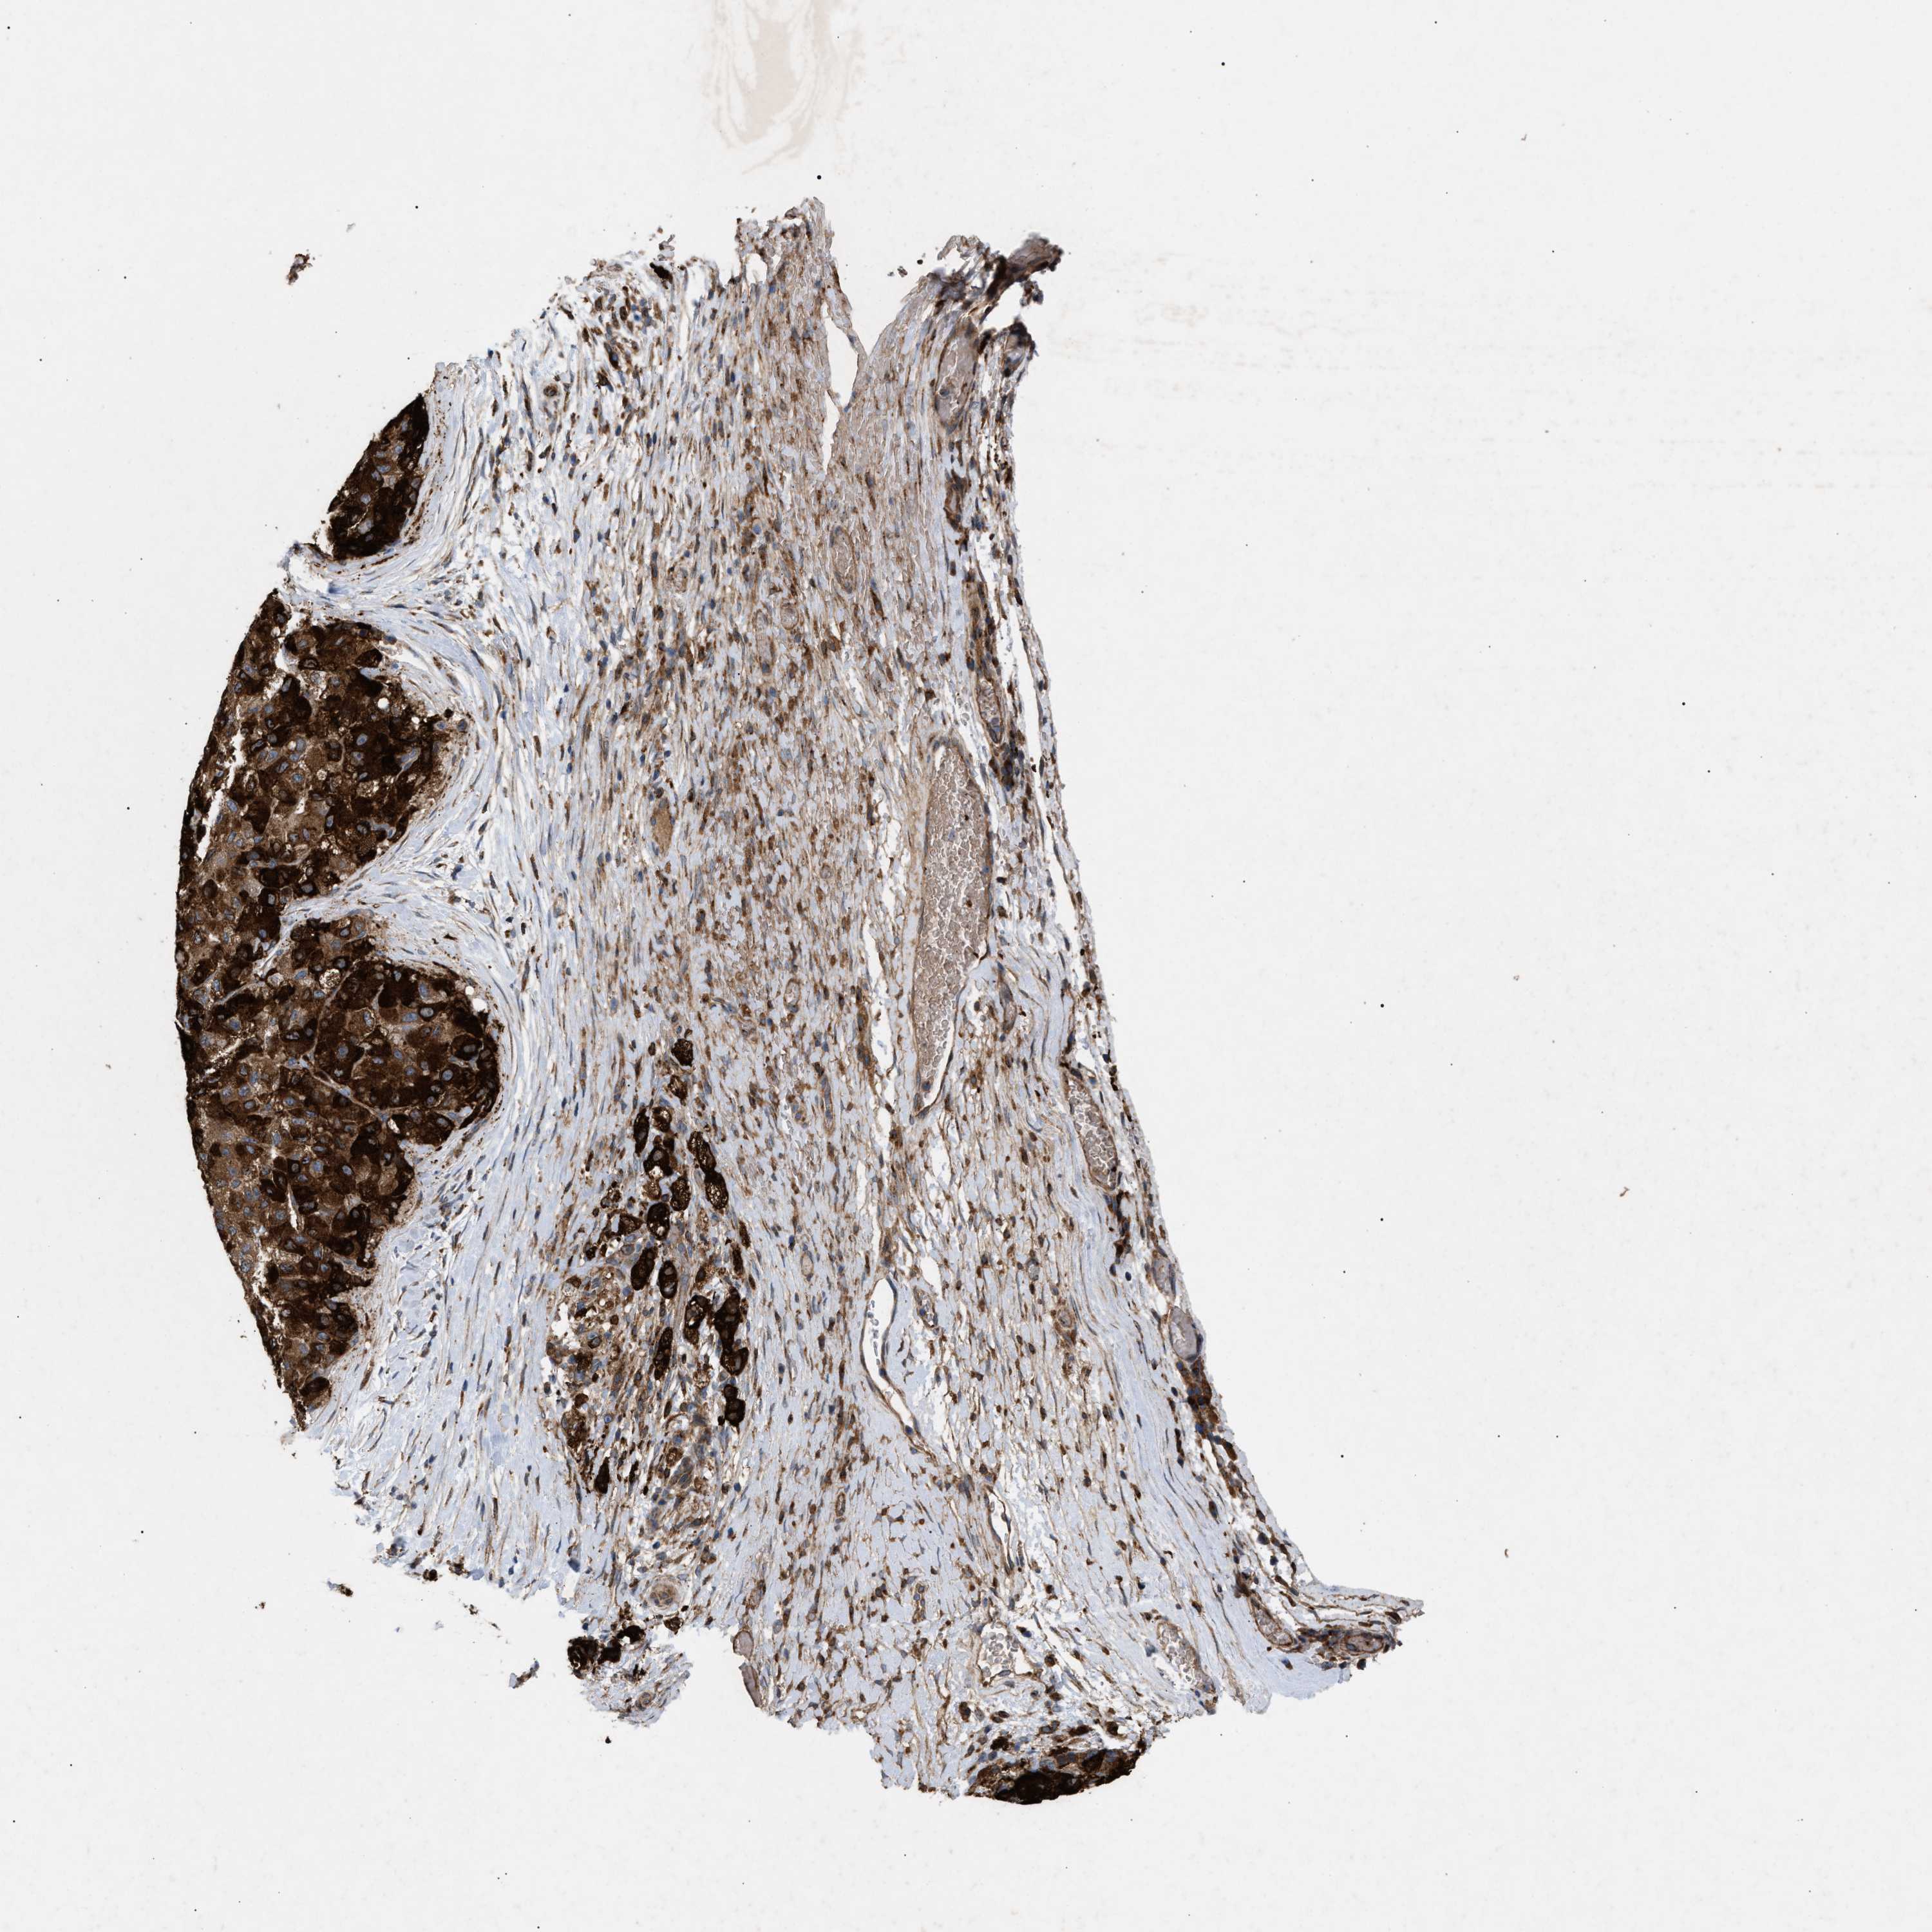

LIVER CANCER - Protein expressioni

A mouse-over function shows sample information and annotation data. Click on an image to view it in a full screen mode. Samples can be filtered based on level of antibody staining by selecting one or several of the following categories: high, medium, low and not detected. The assay and annotation is described here.

Antibody stainingi

Antibody staining in the annotated cell types in the current human tissue is reported as not detected, low, medium, or high, based on conventional immunohistochemistry profiling in selected tissues. This score is based on the combination of the staining intensity and fraction of stained cells.

Each image is clickable and will lead to virtual microscopy that enables deeper exploration of all samples and also displays staining intensity scores, fraction scores and subcellular localization as well as patient and tissue information for each sample.

Antibody HPA019369

Antibody HPA021323

Staining

High

Medium

Low

Not detected

Intensity

Strong

Moderate

Weak

Negative

Quantity

>75%

75%-25%

<25%

None

Location

Nuclear

Cytoplasmic/membranous

Cytoplasmic/membranous,nuclear

Cholangiocarcinoma

Carcinoma, Hepatocellular, NOS